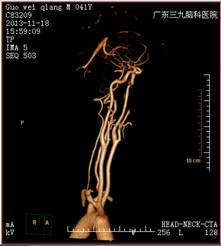

3个月后,患者复查头颅MRI,提示左侧颞后顶叶陈旧性脑梗塞,可能合并有层状坏死(图三),头颈部CTA检查未见异常(图四)。

治疗后CTA(图四)